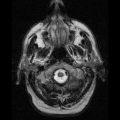

MRI – State of the Art Multimedia Imaging

Multimedia plays a key role in Healthcare for medical procedures. Advancements in healthcare have paved the way for Medical diagnosis for several diseases. In particular, Dementia and Alzheimer Disease (AD) cases rely on multimedia imaging as the main source of diagnostic testing on its patients. Magnetic Resonance Imaging (MRI) is the latest form of technology for patients that suffer from Dementia and AD. Medical studies performed on patients have been able to demonstrate the on-set of the diseases and their progression in the brain.[1] MRI testing has proved to be an essential tool for early diagnosis of AD and Dementia. It is now known that MRI testing can help predict Hippocampus atrophy in the brain which is the leading cause of AD. [2] MRI’s are especially useful for presenting the case to patients and have been involved in case studies that show the progression of the disease that will help the future of predicting and diagnosing patients.